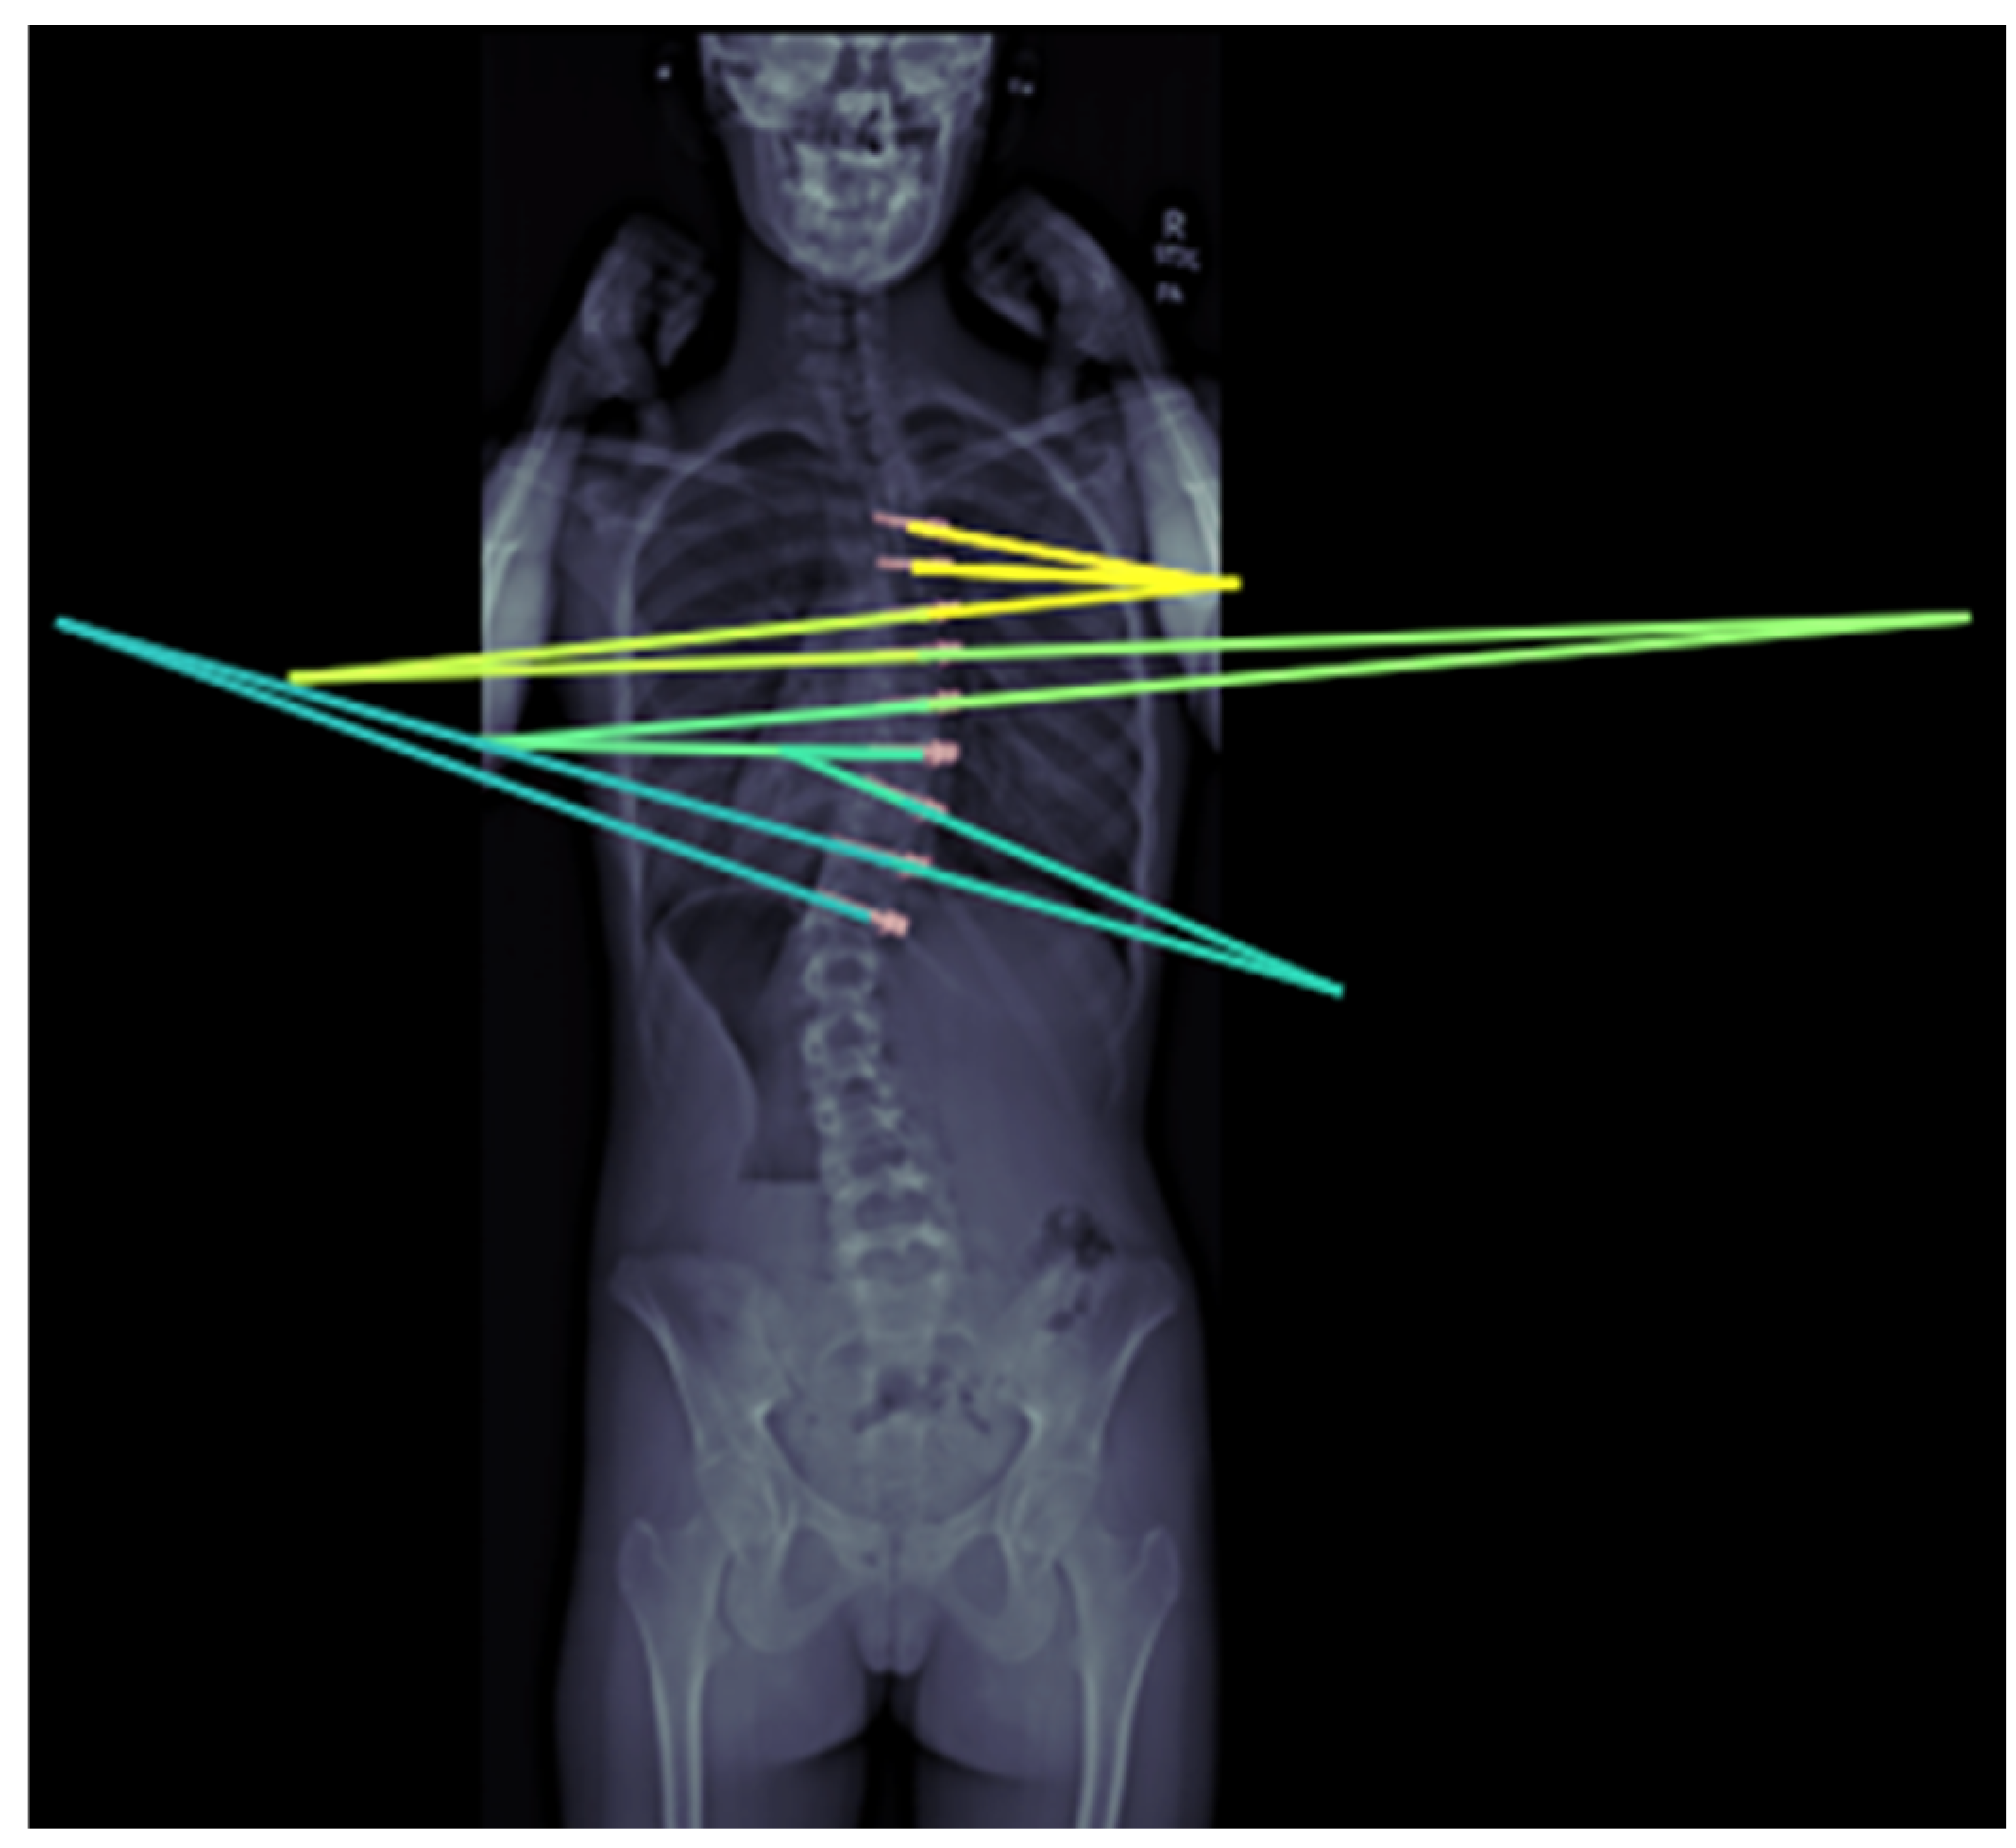

ML can also effectively forecast spinal curve progression, aiding in timely intervention decisions. Using features like initial Cobb angle (

Figure 6) and Risser stage, a Random Forest model has been shown to be able to predict final Cobb angles in 193 AIS patients from a single center with a 4.64° mean absolute error [

15]. Multiple models have also been developed to help identify screw brands, which is helpful for preoperative planning in revision spine surgeries [